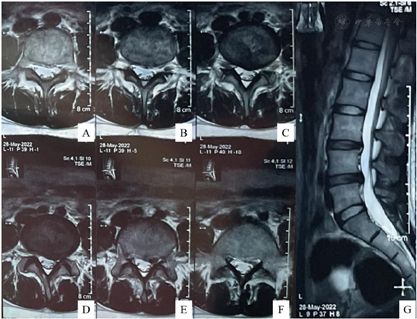

腰椎磁共振提示:L3~L4、L4~L5椎间盘突出,L5~S1椎间盘膨出。腰椎顺列曲度尚可,椎体骨质信号正常,L3~4、L4~5水平硬膜囊受压,脊髓圆锥位置、形态、信号均正常(图1)。